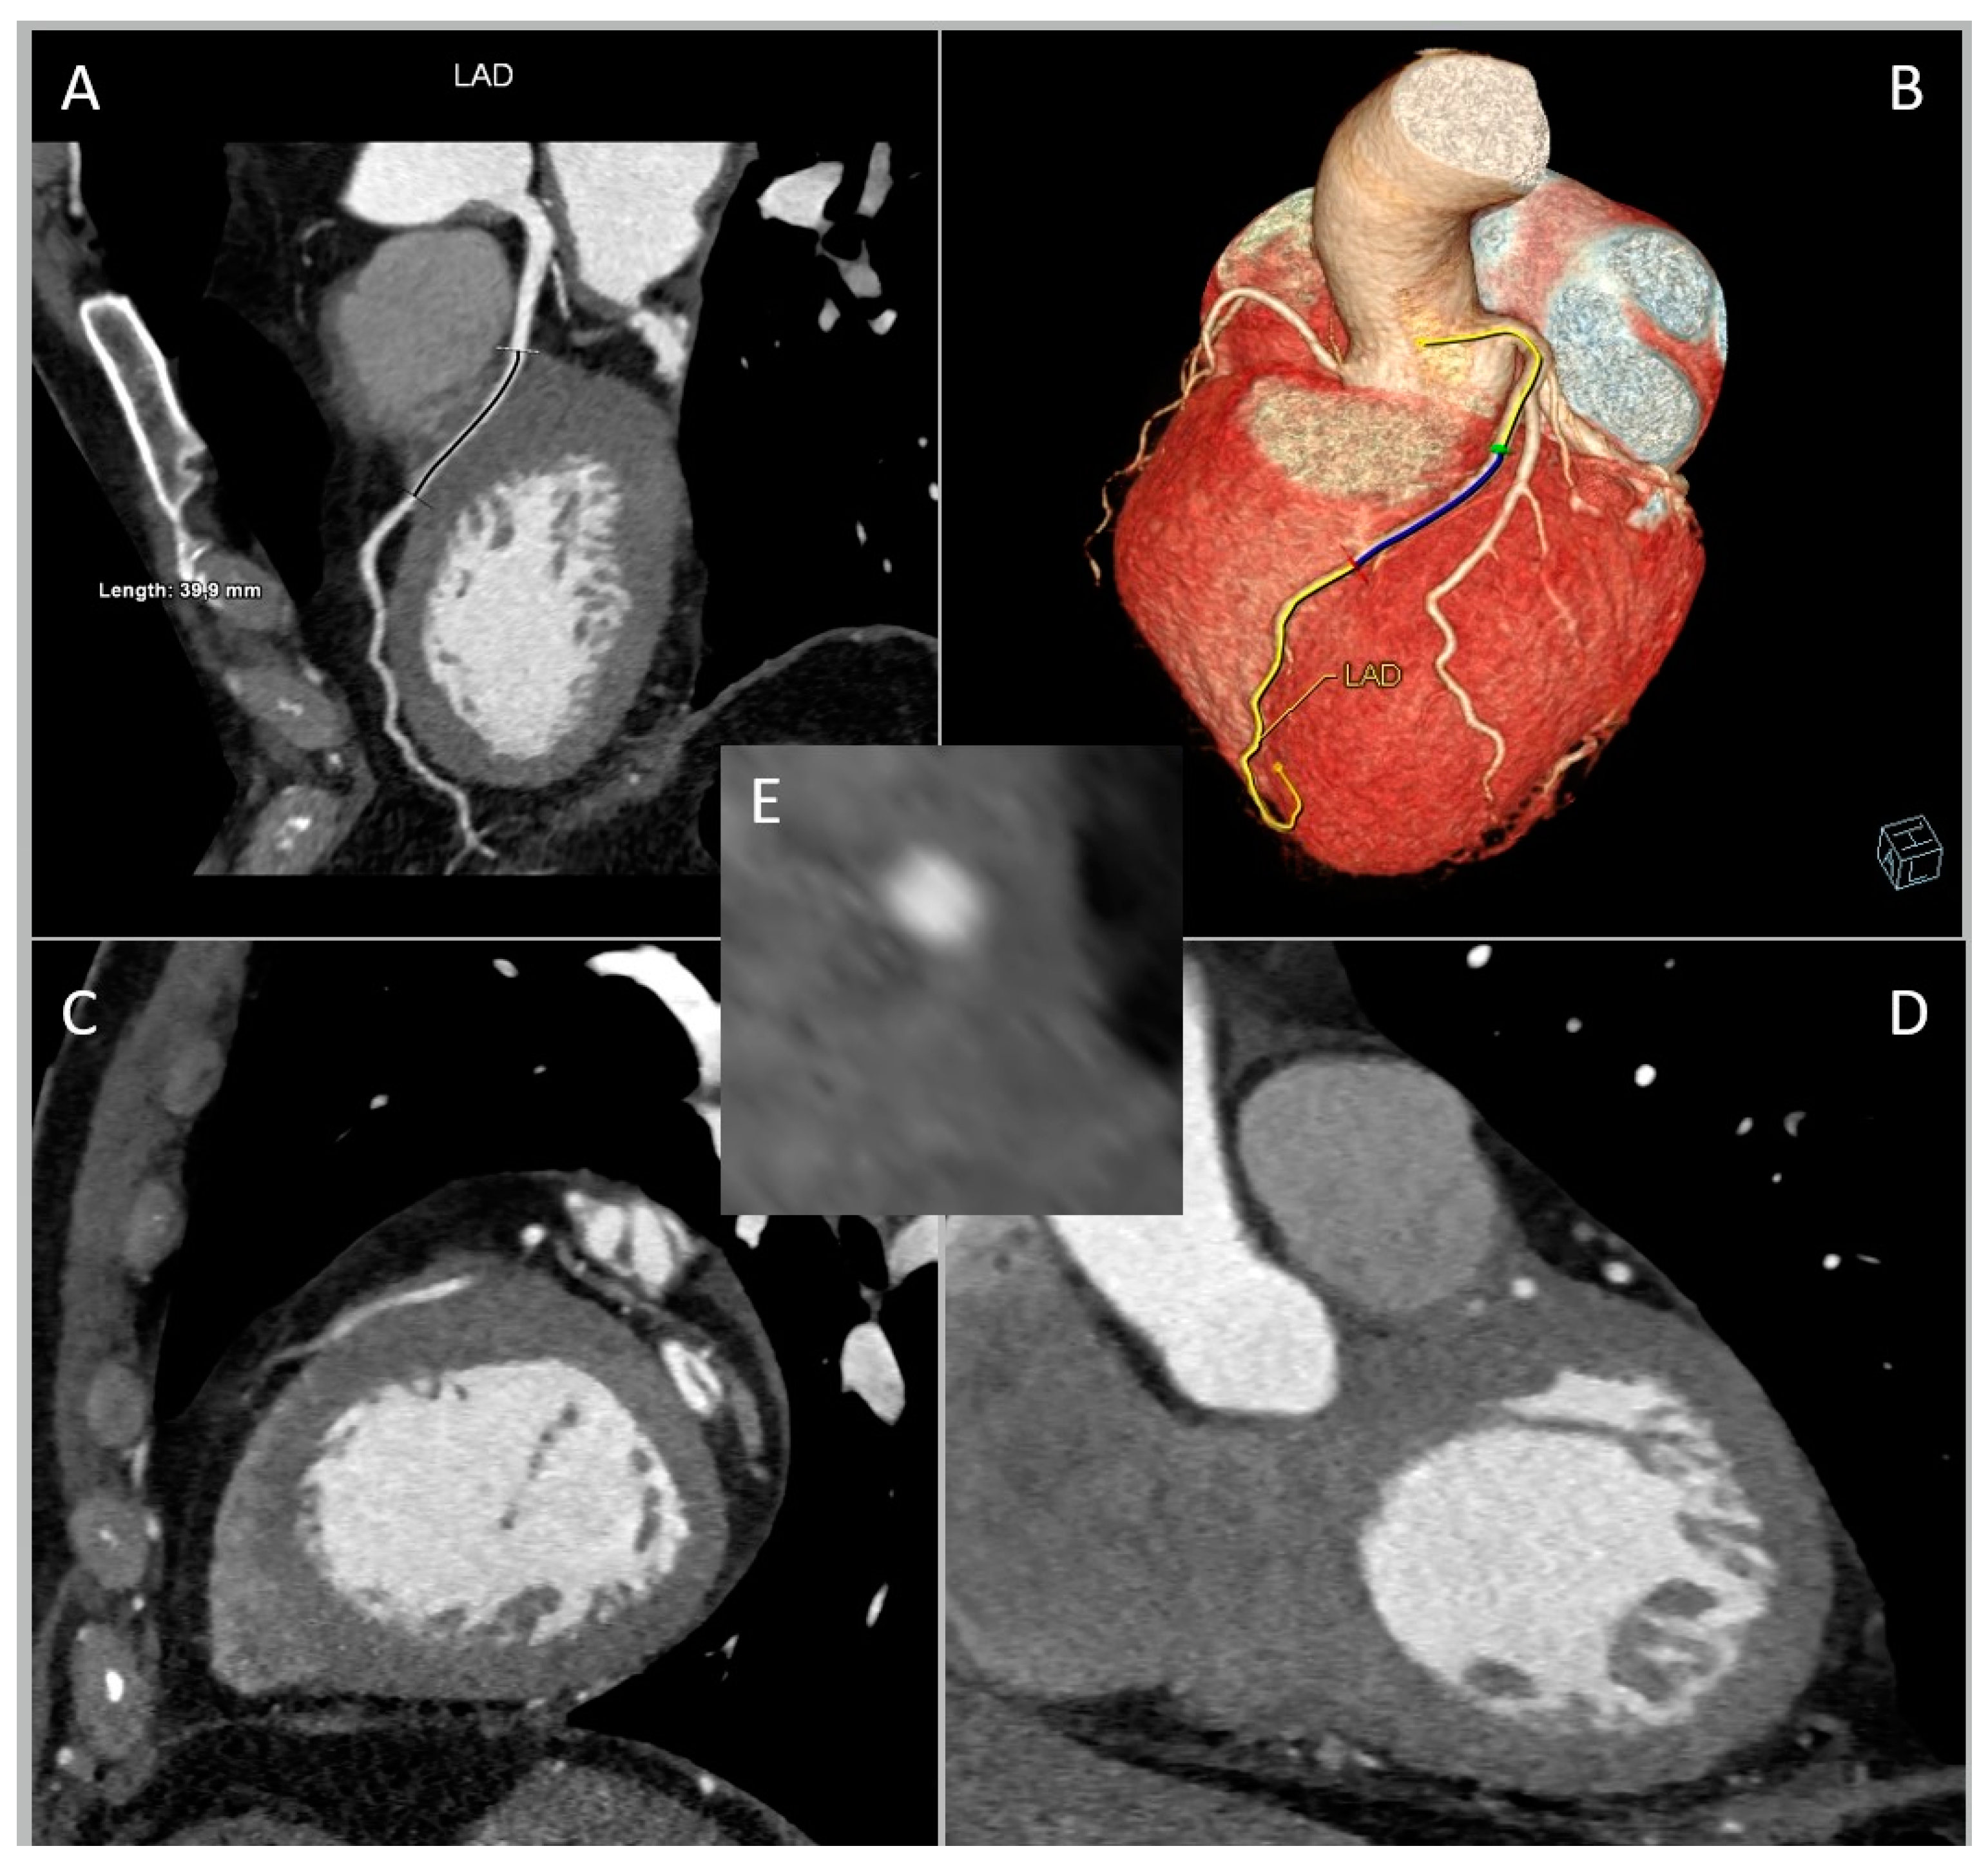

3. Role of CCTA: Anatomical Evaluation